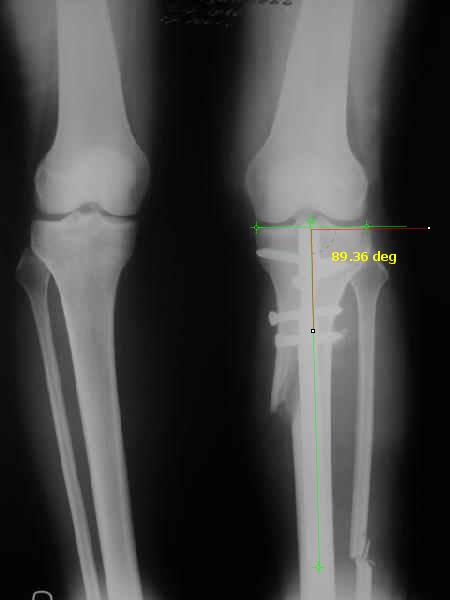

It is very interesting to me that as you have derotated the tibia you have centred the patella, I think and the prox tibia looks much more anatomic.

The analysis in the attached images is direct, just using the tools.

Tibial tilt is perhaps more than you want but the tibial correction is to 90 (very slight over

correction.

Will need full length views to tell us about the hka but it appears neutral.

Measurements took 4 mins